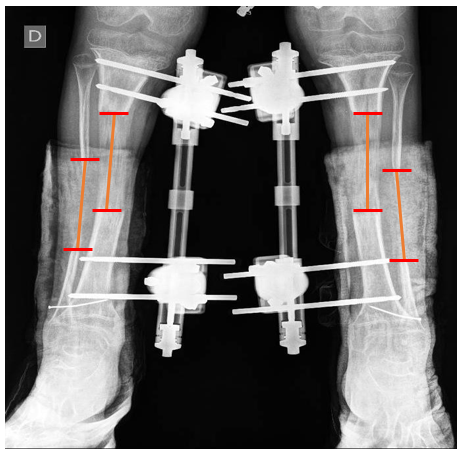

b) The tibiofibular distraction difference (TFDD) (Figure 2), calculated by subtracting total fibular distraction from total tibial distraction at the end of the distraction period

Figure 2: Tibiofibular Distraction Difference (TFDD) Measuring the Tibial and Fibular Distraction at the end of the Distraction Period